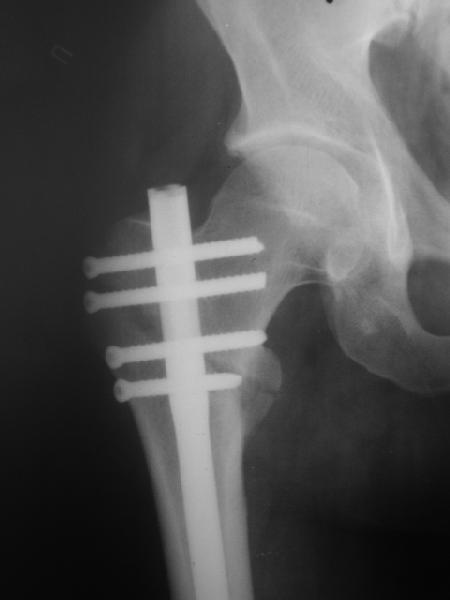

Могу скромно напомнить о существовании стержня нашей модификации.

В частности, на проксимальном конце сделано еще одно дополнительное статическое отверстие. Можно ввести в проксимальном отделе 4 винта, из них 3 статические (2 в круглые отверстия и 1 по нижнему краю овального). Картинки в приложении. На дистальном конце стержня тоже кое-что улучшено. Спрашивайте в аптеках, как говорится. Выпускается предприятием "ЦИТО" (Москва), то есть это малобюджетное решение.